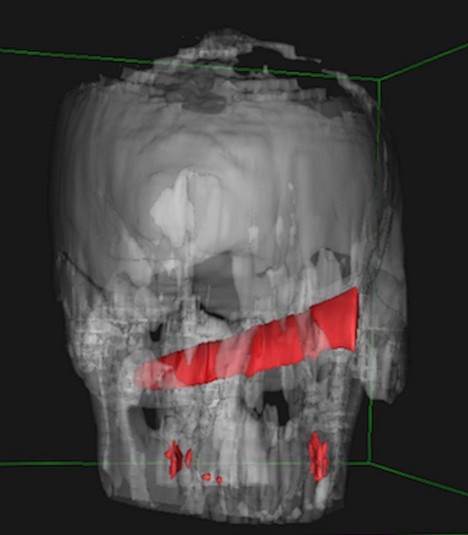

Рентген показал, что нож зашел на 10 см в голову, но не задел ни одной артерии

Удар ножом в глаз он получил во время пьяной драки в баре. После этого пострадавший как ни в чем не бывало отправился домой спать. На следующий день мужчине все же пришлось посетить медучреждение. Лезвия он не заметил, однако голова и глаз очень болели. Рентген показал, что нож зашел на 10 см в голову, но не задел ни одной артерии. Врачи даже решили перенести операцию на четыре дня, пока оформлялись необходимые документы.